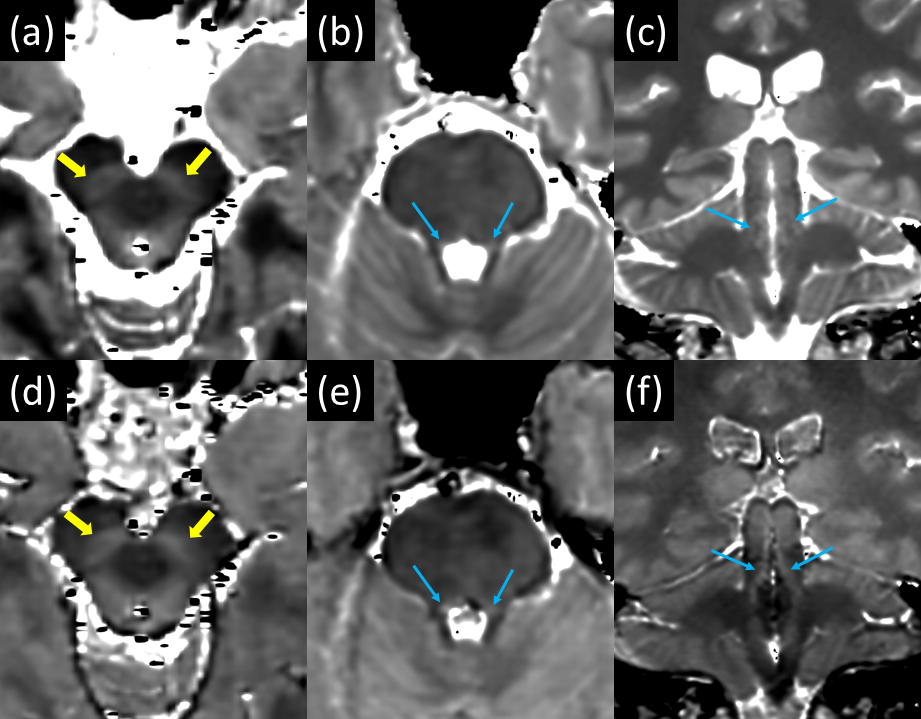

T1 mapping clearly demonstrates both elevated T1 and PD in the SN and LC compared to surrounding tissue [Fig 1]. The mean T1 value from manually drawn ROIs within the left and right substantia nigra over 2 subjects was 714 +/- 68 ms and in the locus coeruleus was 830 +/- 38 ms. This is substantially higher than the mean T1 value from ROIs in myelinated tissue neighboring the SN (572 +/- 40 ms). Thin section, PD-weighted, FSE shows clear, hyperintense signal in the SN and LC [Fig 2] whereas the T1-weighted FSE variant does not clearly visualize the SN and LC. The LC was consistently depicted in all 3 subjects and is well visualized in coronal PD-weighted FSE images [Fig 3].

Figure 3: The LC is clearly depicted (blue arrows) in 3 consecutive subjects when imaged using a thin section coronal PD- plus MT-weighted FSE acquisition.